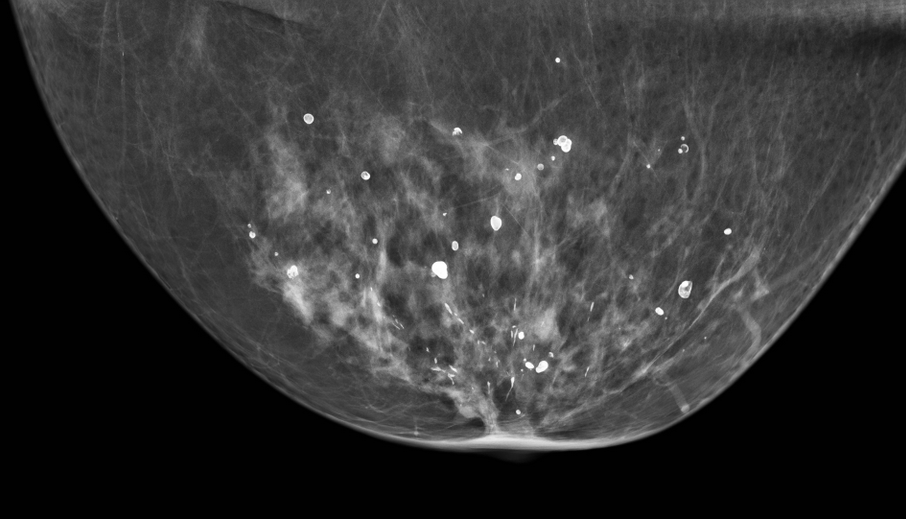

Breast calcifications are common findings on mammography among women over the age of 50 years and about 1 in 10 mammograms of women under 50 years old. The malignant potential of a calcification is judged based on the morphology and distribution of calcifications within the breast. Microcalcifications refers to calcifications ranging from 0.1 millimeter (mm) to 1 mm. Previous findings showed that microcalcification clusters are more likely a sign of malignancy as compared to single microcalcifications (1,2). Improvements in mammography screening using high-resolution imaging techniques and magnification views allowed better detection of microcalcifications. Clinically, microcalcifications mammographic microcalcifications are known as one of the earliest signs of breast cancer, particularly so for the non-palpable breast cancers and are present in nearly one third of all breast cancers (3).

Several papers have published over the years on the association between microcalcifications and risk of breast cancer, however these studies have important limitations (4-8). They did not exclude microcalcifications without a malignant potential (mainly vascular calcifications), did not use an automated measure of calcifications, were underpowered and were mainly based on the case-controls and/or case report studies. In the current study, “Mammographic Microcalcifications and Risk of Breast Cancer”, we used the unique prospective Karolinska Mammography Project for Risk Prediction of Breast Cancer (KARMA) cohort, including 53,273 Swedish women to investigate the association between microcalcification clusters, and risk of overall and subtype specific breast cancer. We also examined if baseline mammographic density influenced the association between microcalcification clusters and risk of breast cancer using an FDA approved and non-reader dependent system (iCAD) for measure of mammographic density and microcalcifications.

Illustration of suspicious microcalcification clusters using iCAD software on cranio-caudal views of a 74 years old woman with a lump in the right breast. iCAD software identified microcalcification clusters with suspicious morphology (iCAD Inc. Caption